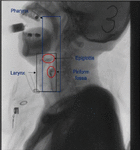

3.5 Confirm ROI Based on X-ray Spine Position

Recognizing the direction of an X-ray photograph is a challenging subject. Normally, the swallowing posture and position of the patient vary, and the position of the body’s oral cavity and the length of the pipe will also vary at different ages, as shown in the following figure. As a result, the acquired video frame sequence is largely related to the radiologist’s shooting situation.

Through observation, we can find that the position of the cervical spine has a relatively high degree of recognition. We can calibrate the position of the cervical spine to track the movement trajectory of the fluid barium. As a model verification and correction link, it will help us to improve the recognition accuracy. Experimental results As shown in the figure below.

images

Figure 9 Taking the cervical spine as the coordinate system.

Figure 10 Taking the cervical spine as the coordinate system (enlarged display).